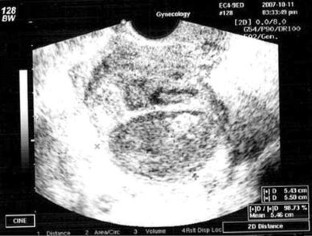

We present a patient with a tubo-ovarian abscess pathologically confirmed to be actinomycosis in a 44-year-old woman with an intrauterine device (IUD). An ultrasound showed that the IUD was imposed on an apparently degenerated myoma. A pelvic MRI was performed to differentiate the uterine findings from a sarcoma. The MRI showed a heterogeneous pelvic mass and a bladder mass suggesting chronic inflammation caused by an organism such as actinomycosis. An exploratory laparotomy was performed, which revealed a right tubo-ovarian mass with abscess formation as well as a bladder mass. A subtotal hysterectomy, right salpingoophorectomy, partial cystectomy, and appendectomy were performed in addition to drainage of the abscess. Histopathological examination revealed a tubo-ovarian abscess and a bladder mass with colonies of actinomycoses.

Fig. 1

Fig. 2

Fig. 3